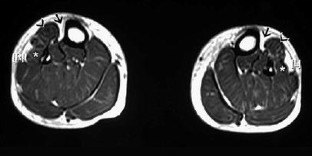

A 35-year-old woman presented with bilateral leg pain on walking that had been present since childhood. Clinical examination showed bilateral absence of the tibialis anterior tendons and the left extensor hallucis longus tendon. Magnetic resonance imaging revealed that signal intensities in the location of the tibialis anterior muscles bilaterally and the left extensor hallucis longus muscle were uniformly high on T1-weighted images, consistent with fat tissue and aplastic muscles: findings not previously reported.

Fig. 2